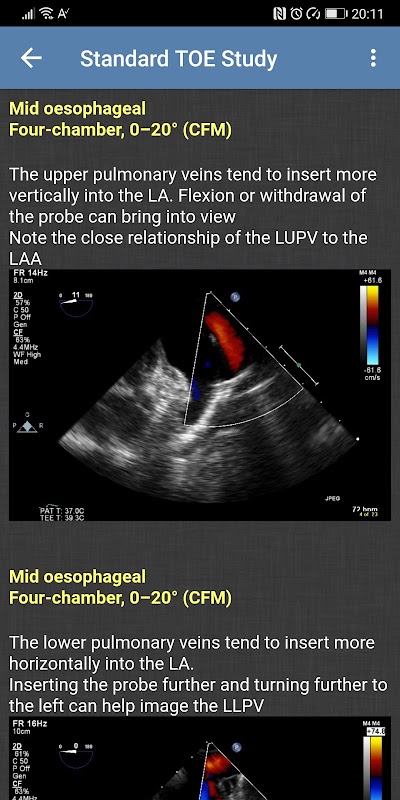

- Стандартное исследование TOE